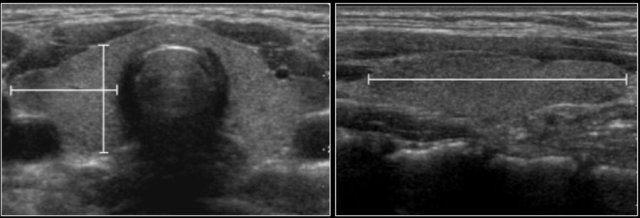

A total of 344 boys from different ethnic backgrounds were studied.

Testicular volume was calculated using the formula:

• Length x Width x Height x 0.523.